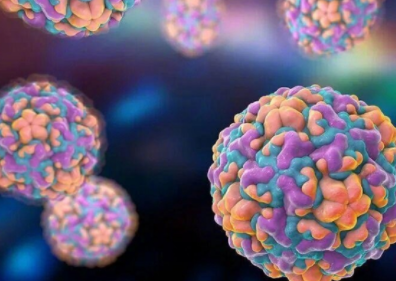

鼻病毒阳性率上升 中疾控提醒:无特效药和疫苗

据国家应急广播报道,寒冬来临,气温骤降,身边不少人开始出现鼻塞、流涕等感冒症状。但检查后却发现,引起症状的并非流感或呼吸道合胞病毒,而是平时较少被提及的鼻病毒。 据中国疾控中心提醒,近期门急诊流感2026-01-12 -